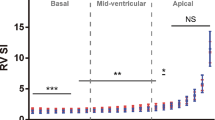

Right and Left Ventricular 24-Segment Transverse Contractility

Non-BAS Fetuses vs Controls

Right ventricular fractional shortening z-score values were significantly less than controls for all mid-chamber and apical segments (Table 8). Left ventricular fractional shortening z-score values were significantly lower than controls for segments 12 to 16 of the mid-chamber and all apical segments (Table 9).

BAS Fetuses vs Controls

Only RV base segments 7 and 8, mid-chamber segments 9 and 10, and apical segments 23 and 24 were significantly less than controls (Table 8). For the LV, only apical segments 19 to 24 were significantly less than controls (Table 9).

Non-BAS vs BAS Fetuses

For the RV, there were significant differences between the 2 groups for segments 9 to 16 for the mid-chamber and segments 17 and 18 of the apical section (Table 8). For the LV there were no significant differences between the 2 groups for all 24 segments (Table 9).